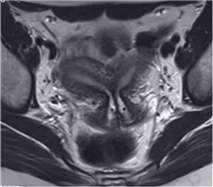

纵隔子宫

最常见,双侧副中肾管融合后,中隔吸收受阻,而形成不同程度的纵隔

分型

完全性:纵隔由宫底达到宫颈内口或外口

部分性:纵隔由宫底未达宫颈内口

需与双角子宫鉴别

纵隔子宫宫底外形正常或轻度凹陷小于1cm,双角子宫则宫底外形凹陷大于1cm

纵隔子宫两角间距小于4cm,双角子宫则大于4cm

纵隔子宫两角夹角小于75°,双角子宫则大于105°

子宫外形正常,宫腔内可见纵隔影将宫腔分离,呈纤维性或肌性信号